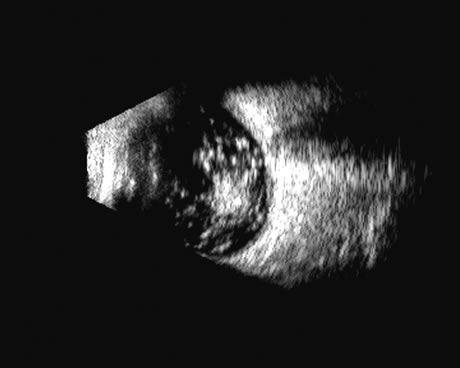

| The retina is a highly reflective surface (specular reflector) and

can be seen to always maintain its connection to the optic nerve, even

when drawn into an organized detachment. It may not be attached

at the ora serrata in giant tears, but otherwise it generally maintains

the two “landmark” attachments of optic nerve and ora serrata (Fig. 13), which can aid in differentiating the retina from the PLM of the

retracted vitreous and from the choroid, in which the detachment may

extend anterior to the ora and rarely extend back behind the vortex veins

to the nerve (Fig. 14).14 Two-dimensional scans through complex three-dimensional structures, such as preretinal membranes and proliferative membranes, can be confusing unless mapped with three-dimensional conceptualization techniques. Bronson and colleagues15 have emphasized three-dimensional thinking. Although new digital three-dimensional ultrasound systems allow direct volume visualization, it remains useful to understand the technique of conceptualizing three-dimensional structures from individual sections.16 Preretinal membranes (Fig. 15), which may resemble traction detachments in thickness and reflectivity, can often be identified by turning the scan plane of the B-scanner at right angles: the disciform retinal elevation is still seen while the linear nature of a traction sheet is revealed.17 A three-dimensional rendering of a retinal detachment can directly show the conformation of three-dimensional structures (Fig. 16), and images of individual planes can be perceived. Schisis can be difficult to differentiate from a peripheral detachment based on echo amplitude, but may be suspected based on location and other clinical factors, such as age and symptomatology. Schisis is usually convex and may have lower amplitude than a retinal echo. |